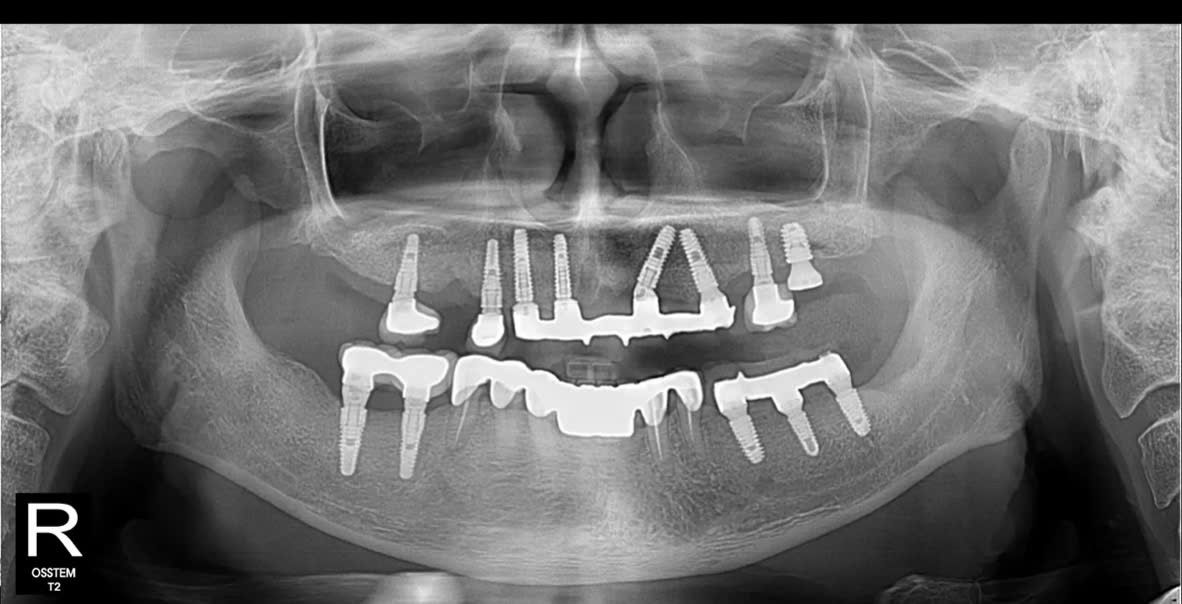

- Hàm trên: Cấy ghép Implant toàn hàm bằng kỹ thuật All-on-5 – giải pháp phục hồi tối ưu giúp tái tạo toàn bộ hàm răng trên chỉ với 5 trụ Implant, mang lại độ vững chắc và thẩm mỹ cao.

- Hàm dưới: Đặt thêm Implant Hiossen (Mỹ) để phục hình lại các răng mất, đảm bảo khả năng chịu lực tốt, tích hợp xương nhanh và tuổi thọ lâu dài.

Toàn bộ quy trình được thực hiện dưới sự hỗ trợ của công nghệ Hansafe độc quyền từ Hàn Quốc giúp cấy ghép chính xác, an toàn, giảm xâm lấn và rút ngắn thời gian hồi phục cho bệnh nhân.

Nhờ ứng dụng công nghệ Hansafe, quá trình cắm trụ Implant diễn ra nhẹ nhàng, hầu như không đau, ít sưng nề. Bác sĩ đảm bảo độ chính xác từng vị trí đặt trụ, đồng thời ghép bổ sung lượng xương cần thiết để đảm bảo độ vững chắc lâu dài.

Sau phẫu thuật, chú Châu được hướng dẫn chăm sóc chi tiết, tái khám định kỳ để theo dõi quá trình tích hợp xương. Dự kiến sau 5–6 tháng, khi trụ Implant ổn định hoàn toàn, bác sĩ sẽ tiến hành lắp răng sứ cố định – hoàn thiện nụ cười và khớp cắn tự nhiên cho chú.